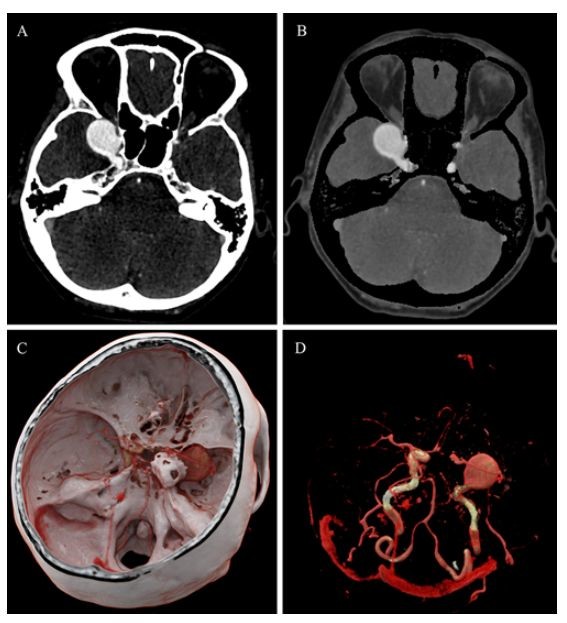

颅内动脉瘤和血管造影阴性蛛网膜下腔出血的影像学综述_医学界-助力

蛛网膜下腔出血

蛛网膜下腔出血的ct平扫表现

入院头颅ct显示双侧蛛网膜下腔,纵裂,基底池脑室广泛出血

蛛网膜下腔出血ct图

ct平扫显示左外侧裂池高密度出血影(红箭),在flair序列上呈斑点状,粗